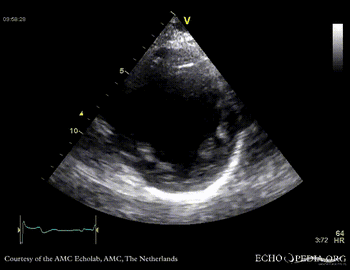

Case 10